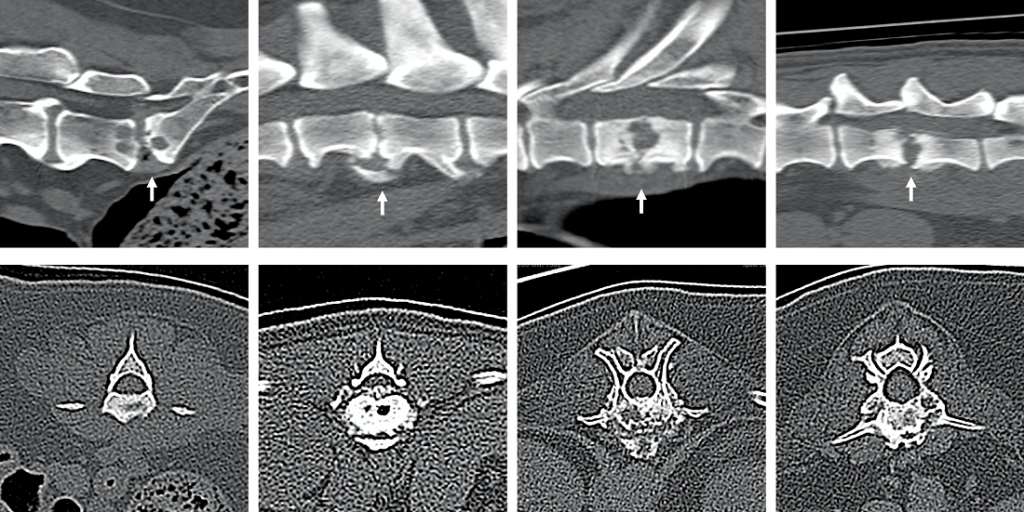

To date MRI has been the imaging modality of choice, with consistent CT imaging features of discospondylitis in dogs and cats not previously reported in detail. However with the increased availability of CT in clinical practice, the research set out to examine CT features that could support the diagnosis of discospondylitis.

- MRI is currently the imaging modality of choice for discospondylitis however with the availability of CT in clinical practice this research was warranted. CT presents some advantages over MRI in the diagnosis of discospondylitis such as excellent depiction of bone, FNA guidance and enhanced utility in preoperative planning of spinal surgery in instances of subluxation or fractures.

- CT imaging features that can support the diagnosis of discospondylitis when performed in all three planes although equivocal cases on CT might still require MRI. Prior to this study, CT imaging features of discospondylitis in dogs and cats had not been reported.

Gomes, SA, Targett, M, Lowrie, M. Computed tomography features of discospondylitis in dogs. J Vet Intern Med. 2022; 36( 6): 2123- 2131.[1]